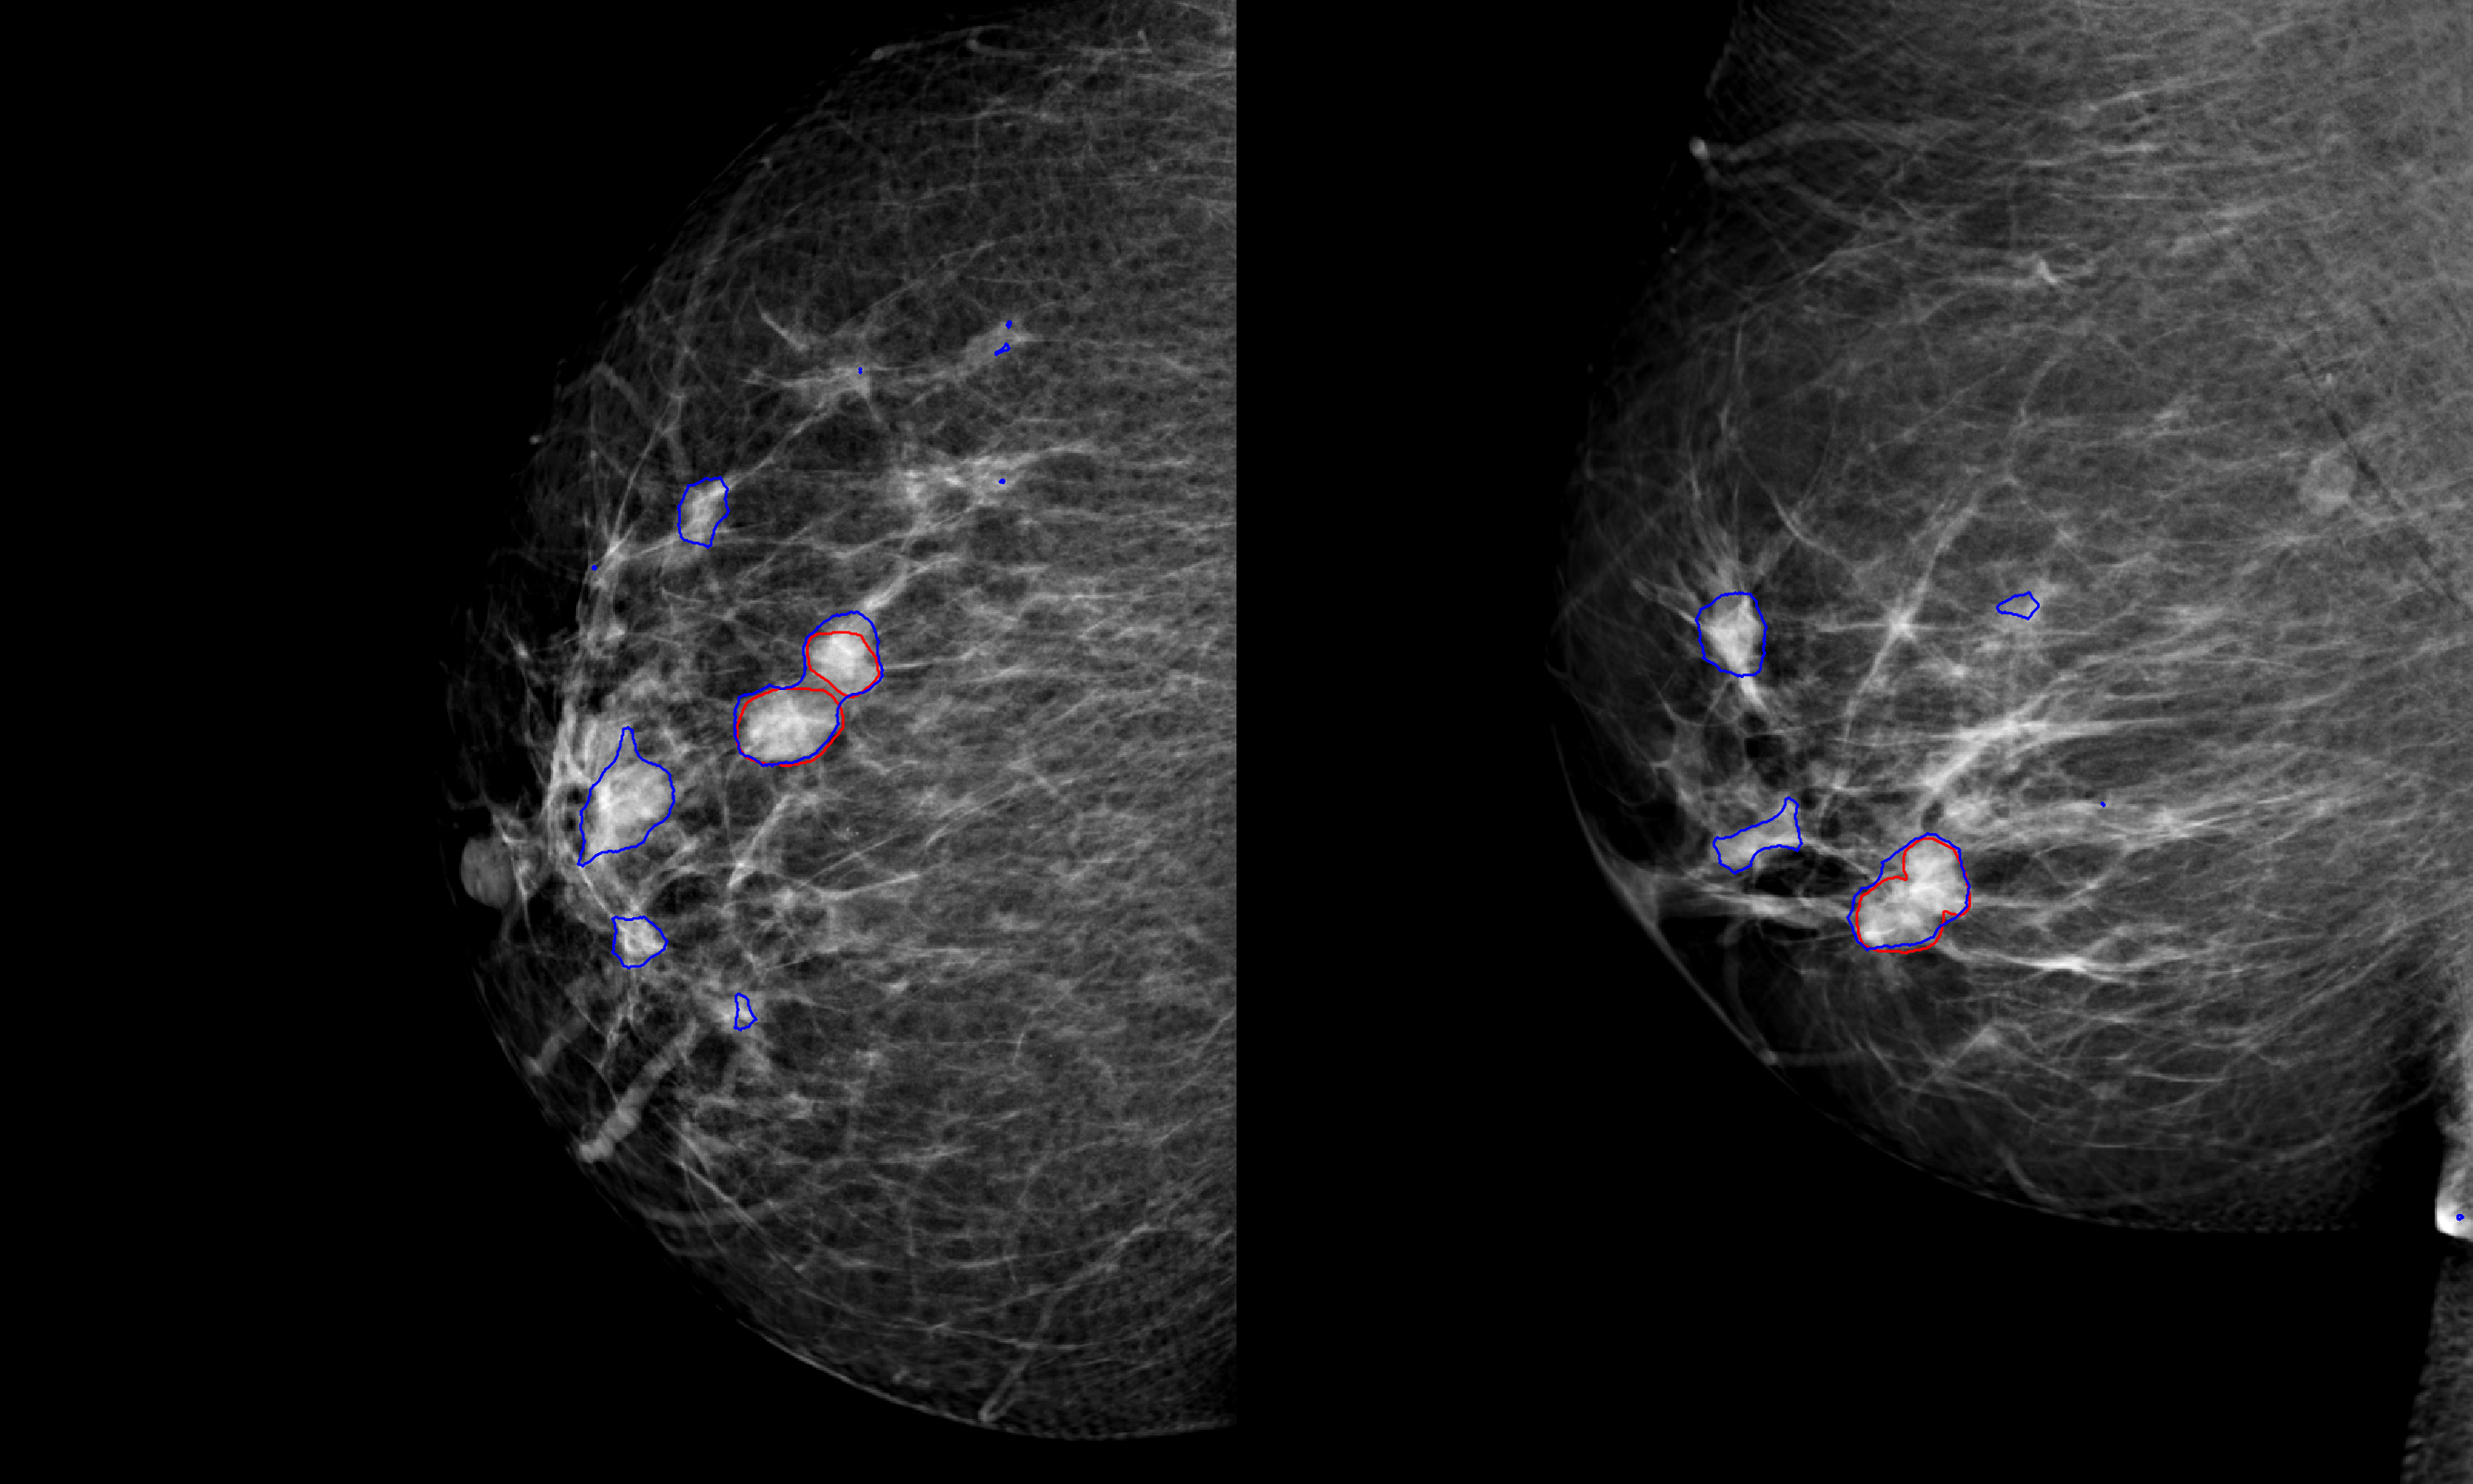

Images were preprocessed in three steps. First, an energy band normalization technique was applied [6]. To homogenize the pixel size across different vendors, images were downscaled to after applying a Gaussian filter. Finally, pixel values were scaled to the range . Examples of preprocessed images with outlined lesions are shown in Figure 1.

All cases with malignant lesions were verified by histopathology and manually annotated and segmented under the supervision of an expert breast radiologist, with access to other breast imaging exams, radiological and histopathological reports. More than of the lesions had a maximal bounding box diameter of and on average had a height/width ratio of about . The negative cases were verified by at least two years of negative follow-up imaging exams.